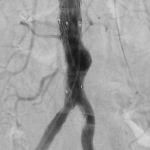

This was treated by interventional radiology using pinhole techniques. A small access was placed in the right groin artery (right CFA) and repair was done endovascularly using a Medtronic Renu cuff. The device was placed percutaneously and the access site closed using Proglide closure device by Abbott.

Whole procedure done under local anaesthetic and completed in 20 minutes. Patient was asymptomatic following the procedure and discharged the following day.